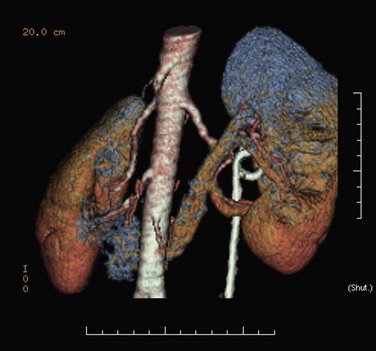

Use of a cautery wire balloon for management of UPJ obstruction was first reported in a clinical series by Chandhoke and colleagues in 1993. Use of this device gained initial acceptance by many clinicians because standard cystoscopic techniques and real-time fluoroscopy are all that is necessary for its use. Because the procedure is guided fluoroscopically, such vessels may increase the risk of hemorrhage after activation of the cautery wire balloon. Some authors recommended preoperative imaging for such vessels with relatively noninvasive techniques such as CT or three-dimensional CT angiography (Fig. 41–12) (Streem and Geisinger, 1995; Quillin et al, 1996; Nakada et al, 1998; Herts et al, 1999; Nakada, 2000). Nadler and colleagues (1996) reported on 28 patients 2 or more years after cautery wire balloon endopyelotomy. With a mean follow-up of 32.5 months, subjective improvement was noted in 61% of patients, and 81% had a patent UPJ on the basis of diuretic renography or Whitaker testing. More recent studies have demonstrated lower success rates than these initial series (32% to 63%) and perhaps that high-grade hydronephrosis has a negative impact on success (Albani et al, 2004; Sofras et al, 2004). El-Nahas and colleagues reported a small prospective randomized trial comparing retrograde ureteroscopic endopyelotomy to the hot-wire balloon endopyelotomy in 40 patients. Although not statistically significant, they found superior success rates (85% compared with 65%) and lower complication rates with the ureteroscopic endopyelotomy (El-Nahas et al, 2006). Ponsky and Streem reported on 64 patients undergoing either ureteroscopic endopyelotomy or hot wire balloon endopyelotomy and found equivalent success rates with both procedures yet higher major complication rates in the cautery wire balloon endopyelotomy, specifically transfusion and selective embolization (Ponsky and Streem, 2006). The major complication associated with cautery wire balloon incision is hemorrhage. Although injury to crossing vessels has been reported using the cutting balloon catheter, strict adherence to lateral incision principles minimizes this risk (Sampaio et al, 1993; Streem and Geisinger, 1995; Wagner et al, 1996). In addition, although some believe crossing vessels hinder success rates primarily, others believe hemorrhage is a real concern (Aslan et al, 1998). Currently, improved ureteroscopic instrumentation and the benefits of direct endoscopic visualization make ureteroscopic endopyelotomy the more pervasive retrograde approach.

Figure 41–12 Spiral CT angiography with three-dimensional reconstruction clearly identifies an accessory lower pole crossing vessels at the level of the ureteropelvic junction (UPJ) in a patient with UPJ obstruction. This case was managed successfully with laparoscopic pyeloplasty.